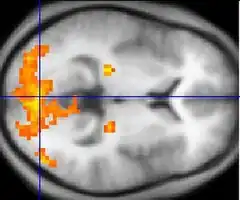

Asperger syndrome appears to result from developmental factors that affect many or all functional brain systems, as opposed to localized effects.[72] Although the specific underpinnings of AS or factors that distinguish it from other ASDs are unknown, and no clear pathology common to individuals with AS has emerged,[12] it is still possible that AS's mechanism is separate from other ASDs.[73] Neuroanatomical studies and the associations with teratogens strongly suggest that the mechanism includes alteration of brain development soon after conception.[68] Abnormal fetal development may affect the final structure and connectivity of the brain, resulting in altered neural circuits controlling thought and behavior.[74] Several theories of mechanism are available; none are likely to provide a complete explanation.[75]

The underconnectivity theory hypothesizes underfunctioning high-level neural connections and synchronization, along with an excess of low-level processes.[70] It maps well to general-processing theories such as weak central coherence theory, which hypothesizes that a limited ability to see the big picture underlies the central disturbance in ASD.[76] A related theory—enhanced perceptual functioning—focuses more on the superiority of locally oriented and perceptual operations in autistic individuals.[77]

The mirror neuron system (MNS) theory hypothesizes that alterations to the development of the MNS interfere with imitation and lead to Asperger's core feature of social impairment.[71][78] One study found that activation is delayed in the core circuit for imitation in individuals with AS.[79] This theory maps well to social cognition theories like the theory of mind, which hypothesizes that autistic behavior arises from impairments in ascribing mental states to oneself and others;[80] or hyper-systemizing, which hypothesizes that autistic individuals can systematize internal operation to handle internal events but are less effective at empathizing when handling events generated by other agents.[81]